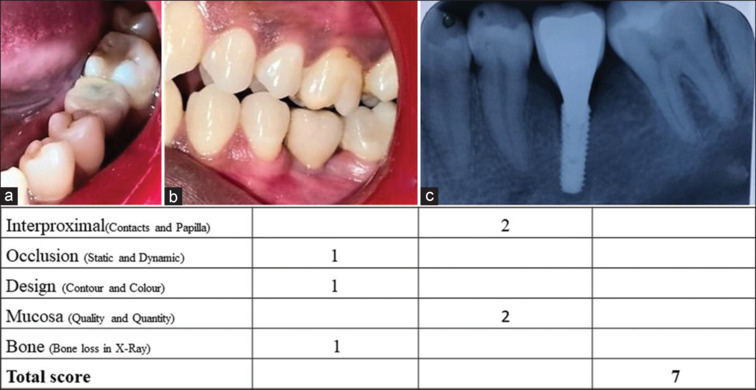

Materials and methods: Fifteen patients with cement-retained single-implant crowns in the posterior region of the jaws were included. Eight examiners, two prosthodontists, two periodontists, two oral surgeons, and two orthodontists evaluated 15 photographs of single-unit implant crowns during the 1-year follow-up examination. The examiners assessed the photographs for FIPS, which includes five parameters for objectively evaluating the single-unit implant crowns. Assessments were performed twice at a gap of 4 weeks.

Results: The mean total FIPS scores for all included examiners were 7.133 for time T1 and 7.074 for time T2, showing a strong Pearson correlation coefficient for intra-examiner reproducibility. No significant difference was analyzed among different specialties with statistically significant values of the Kruskal-Wallis test.